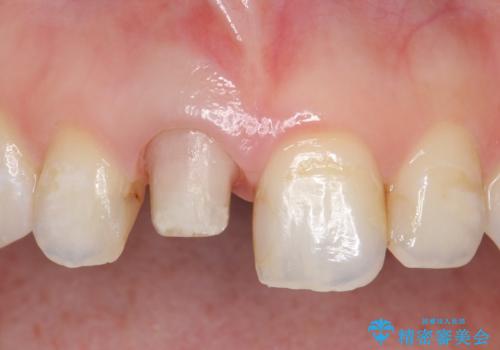

- 右上1番目の歯の変色が気になると来院された方の症例です。

検査の結果、右上1の歯は失活(歯の神経が死んでいること)していたため根管治療を行いました。

その後オールセラミッククラウン(スペシャル)による補綴を行いました。

今回用いたオールセラミッククラウンはジルコニアフレームという白い素材の上にセラミックを盛っているため、審美性が非常に高いのが特徴です。

また、ジルコニアは人工ダイヤモンドの材料にも使われているほど高い強度を持っており、そのためオールセラミッククラウンは審美性だけでなく、奥歯やブリッジの補綴も可能とするクラウンです。